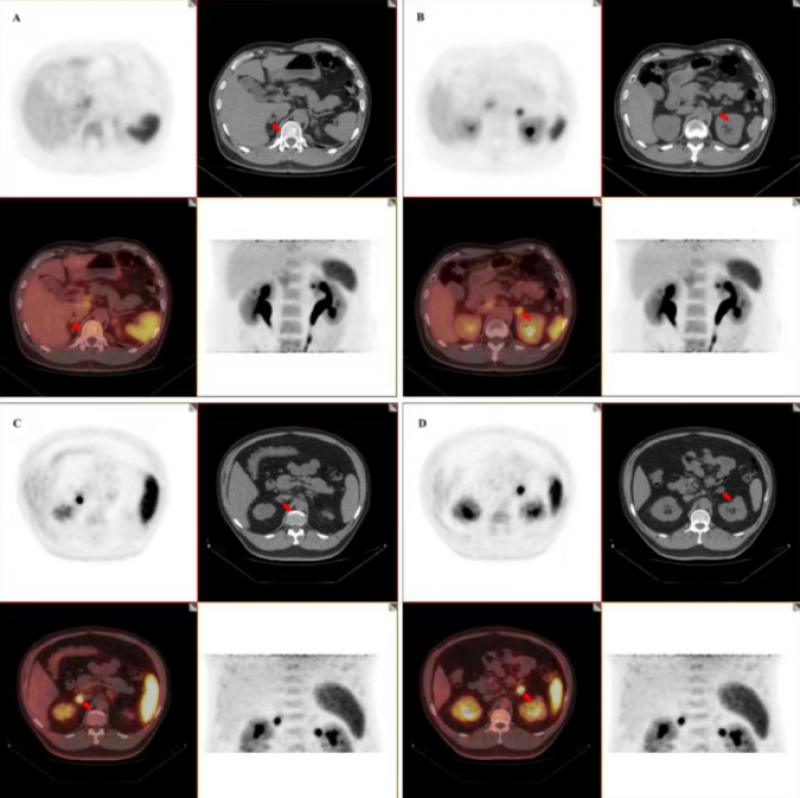

在诊断层面,当常规影像学检查难以定性时,核医学功能成像成为关键工具。例如,全身骨显像(骨扫描)能够高灵敏度地筛查多发性骨转移,是发现前列腺癌、乳腺癌等恶性肿瘤骨转移的首选方法之一。而正电子发射断层扫描/计算机断层扫描(PET/CT)技术,特别是使用¹⁸F-FDG作为示踪剂的PET/CT,能够同时提供骨病变的精确解剖位置和代谢活性信息,对于鉴别侵袭性恶性肿瘤(如骨肉瘤、尤文肉瘤、转移瘤)与良性病变或感染具有重要价值。此外,诸如⁶⁸Ga-PSMA PET/CT等新型靶向显像技术,可对前列腺癌骨转移进行更特异的精准定位。

临床实践中,骨肿瘤的初步鉴别可依据年龄、部位和影像学征象等线索。值得注意的是,对于40岁以上患者,即使影像学表现“良性”,也需高度警惕转移瘤和多发性骨髓瘤的可能,此时核医学检查(如PET/CT)的价值尤为突出。核医学通过提供病灶的生物学功能信息,与传统影像形成有力互补,共同构建了骨肿瘤从筛查、诊断、分期到靶向治疗的完整技术链条,体现了核技术在肿瘤精准医疗领域的核心价值。